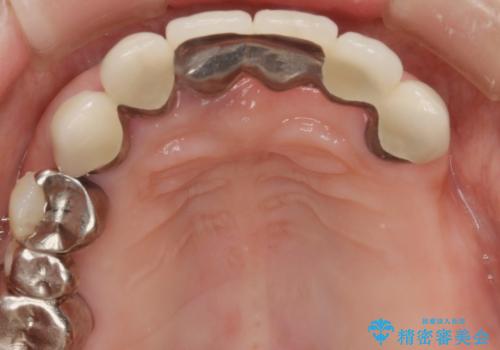

歯周病 全顎治療

- 前歯の見た目、入れ歯による噛めないことの改善を求めて来院されました。

検査により全顎的な歯周病治療、欠損のインプラント補綴、根管治療が必要な状態であることをお伝えし、治療を計画します。